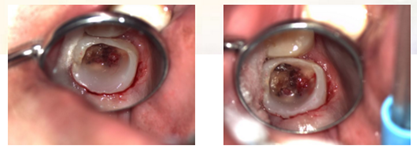

检查:26冠部大面积龋损,仅余近中颊侧残壁,残余牙体颜色变暗,牙龈增生至缺损牙体组织内部,髓腔内炎性牙髓组织增生呈息肉状。探诊(+),冷诊(±),叩诊(-),无松动。

1、局麻下,Er-YAG激光切除增生牙龈

2、使用组织排开橡皮障夹(#B-1)上橡皮障,障布边缘翻转,隔离牙龈,封闭患牙。

7、初步恢复牙体完整性后上橡皮障,开髓,3% NaClO冲洗,揭除髓顶,修整开髓洞形,去除髓腔牙髓组织。

8、定位根管口后,8#K锉结合根管冠方预敞,逐步探查,四根管通畅。因操作时间过长,未作根管预备,氢氧化钙糊剂暂封根管一周,玻璃离子暂封。